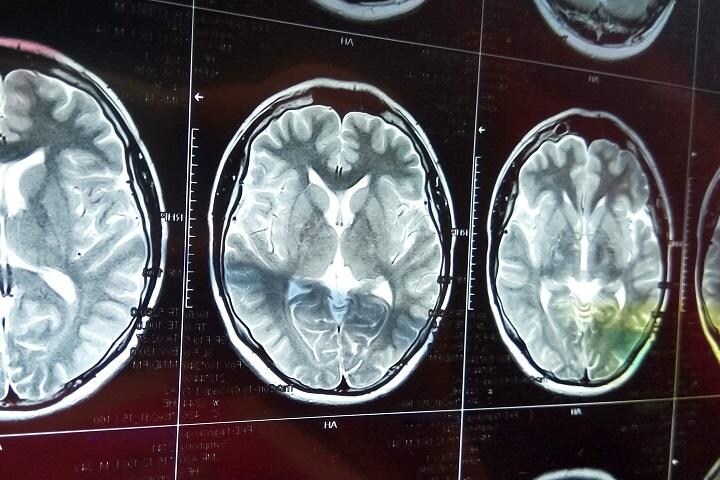

今年は人類の意識の進化にとってブレークスルーの年だった、とTransTech Conferenceを主宰する心理学者Jeffery A. Martin博士は語る。まだ技術的に不安定で政府の認可プロセスなどに時間がかかるが、経会陰超音波による脳への直接刺激が人類の意識進化に有効であることが分かったという。同博士によると、瞑想などの長期にわたる修行をしなくても、この技術で「恐れ」「欠乏の心」から「満たされた心」に簡単に移行できるようになるほか、てんかんやアルツハイマー病などの神経疾患の治療にも役立つとしている。5年から10年以内の実用化を目指すという。